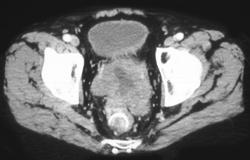

Diagnosis

Appendicitis